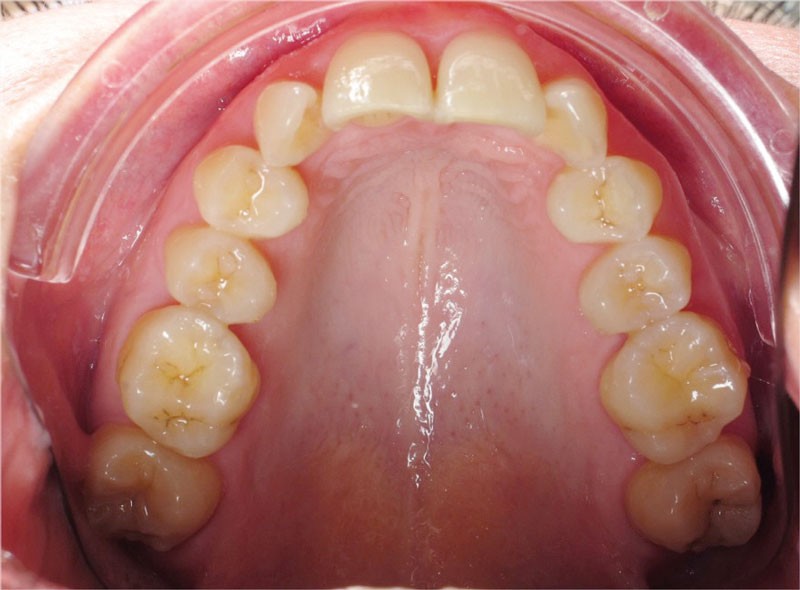

De larges surélévations postérieures étalées ont été mises en place et la patiente a porté des élastiques précoces suivant les principes de la technique Damon. Les 14 et 24 rempliront le rôle des 13 et 23.

Les objectifs de traitement ont été remplis. Nous avons observé un excellent contrôle du torque et une absence de perte de l’occlusion postérieure grâce à la technique Insignia.